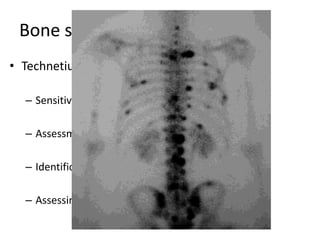

Bone scanning

• Technetium-99m (99m Tc) bone scanning:

– Sensitive for detection of occult lesions

– Assessment of the biologic activity of lesions

– Identification of other sites

– Assessing response to therapy